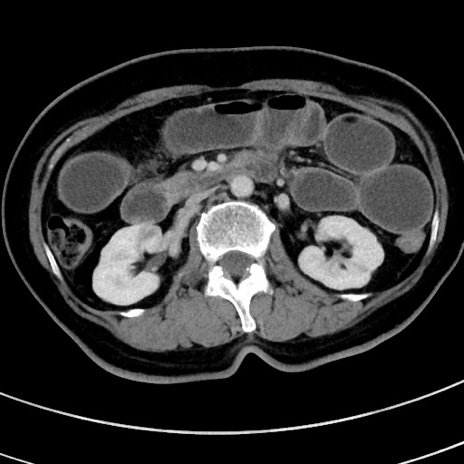

症例9(横断像)

【症例】 60歳代女性

【主訴】むかつき、みぞおちの痛み

【現病歴】3日前よりむかつきがあり、食事がとれない。

【既往歴】糖尿病

【身体所見】発熱なし、心窩部圧痛軽度あるも、腹膜刺激症状なし。

【データ】WBC 7400、CRP 1.92